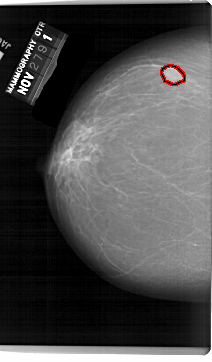

A_1519_1.RIGHT_MLO

RIGHT_CC LINES 6316 PIXELS_PER_LINE 3886 BITS_PER_PIXEL 12 RESOLUTION 43.5 NON_OVERLAY

FILE: A_1519_1.LEFT_CC.OVERLAY

TOTAL_ABNORMALITIES 1

ABNORMALITY 1

LESION_TYPE MASS SHAPE OVAL MARGINS OBSCURED

ASSESSMENT 4

SUBTLETY 5

PATHOLOGY BENIGN

TOTAL_OUTLINES 1

BOUNDARY